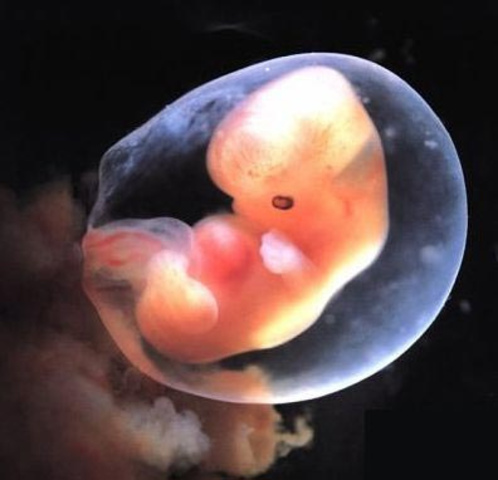

week 10

Though he's barely the size of a kumquat — a little over an inch or so long, crown to bottom — and weighs less than a quarter of an ounce, your baby has now completed the most critical portion of his development. This is the beginning of the so-called fetal period, a time when the tissues and organs in his body rapidly grow and mature